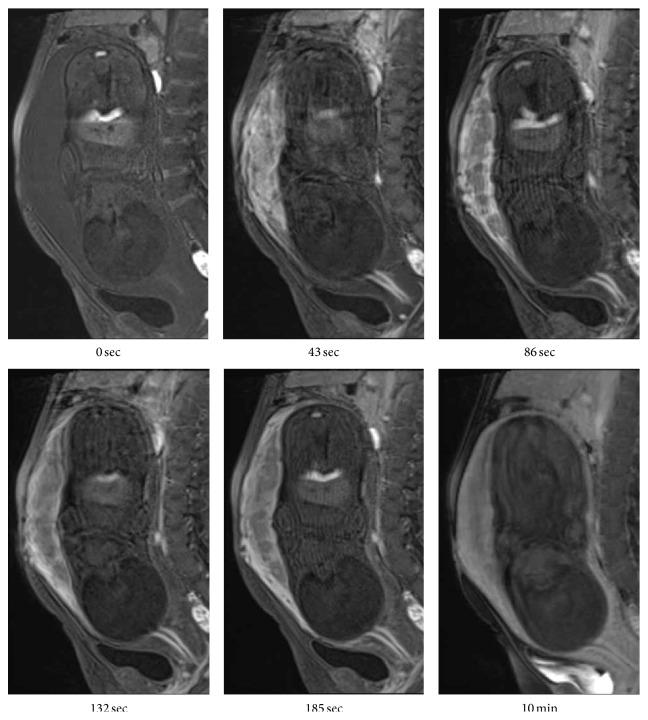

Background. We experienced a rare case of a pregnant woman with Klippel-Trénaunay syndrome complicated with diffuse venous malformation of the uterus. This is the first report on the usefulness of dynamic contrast-enhanced-MRI for the diagnosis of diffuse venous malformation of the uterus. Case Presentation. A 23-year-old woman presented with convulsions and talipes equinus position of both lower limbs at 11 weeks of gestation. At 27 weeks, ultrasonography demonstrated tubular echolucent spaces throughout the myometrium. Dynamic MRI at 37 weeks revealed that the myometrial lesion was enhanced slowly and showed homogeneous enhancement even on a 10 min delayed image. Taken together with unilateral foot hypertrophy, varices, and port-wine stain, the patient was diagnosed as having Klippel-Trénaunay syndrome complicated with diffuse venous malformation of the pregnant uterus. The patient underwent elective cesarean section because of severe dystonia. The lower uterine segment was thickened and heavy venous blood flow was observed at the incision. Histological diagnosis of the myometrial biopsy specimen was venous malformation. Conclusions. Both diffuse venous malformation and Klippel-Trénaunay syndrome during pregnancy can involve considerable complications, in particular, massive bleeding during labor. Women who suffer from this syndrome should be advised about the risk of complications of pregnancy.

背景。我们遇到了一例罕见的患有克-特综合征并伴有子宫弥漫性静脉畸形的孕妇。这是关于动态对比增强磁共振成像(dynamic contrast-enhanced-MRI)对子宫弥漫性静脉畸形诊断价值的首例报告。病例报告。一名23岁女性在妊娠11周时出现惊厥及双下肢马蹄内翻足姿势。27周时,超声检查显示子宫肌层内有管状无回声区。37周时的动态磁共振成像显示子宫肌层病变强化缓慢,即使在延迟10分钟的图像上也呈均匀强化。结合单侧足部肥大、静脉曲张和葡萄酒色斑,该患者被诊断为患有克-特综合征并伴有妊娠子宫弥漫性静脉畸形。由于严重肌张力障碍,患者接受了择期剖宫产。子宫下段增厚,在切口处观察到大量静脉血流。子宫肌层活检标本的组织学诊断为静脉畸形。结论。妊娠期间的弥漫性静脉畸形和克-特综合征都可能涉及相当多的并发症,尤其是分娩时的大量出血。应告知患有该综合征的女性妊娠并发症的风险。